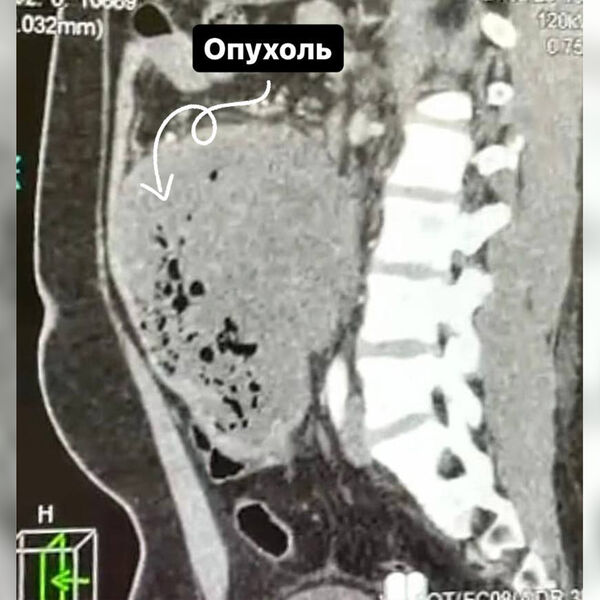

Врачи Долгопрудненской больницы прооперировали 21-летнего пациента со злокачественной опухолью размером 15 см, новообразование мужчина принял за кишечную инфекцию. Об этом сообщает минздрав Московской области.

«Ситуацию осложняла локализация опухоли, она находилась в труднодоступном для удаления месте — между аортой и нижней полой веной. Под общим наркозом мы удалили 15-сантиметровое образование вместе с участком кишки», — рассказал заведующий хирургическим отделением больницы Сергей Лисин.